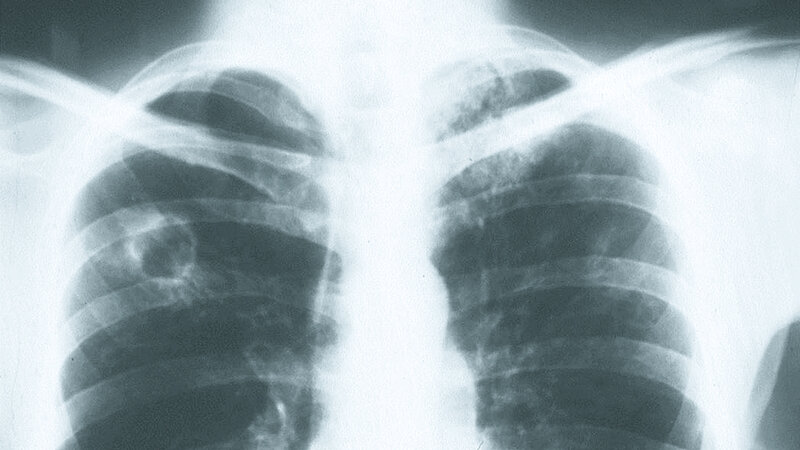

Tuberkulose am Arbeitsplatz

Das Auftreten von Tuberkulose-(TB-)Fällen in Arztpraxen und Krankenhäusern führt bei Mitarbeitern und Kontaktpatienten oft zur Beunruhigung. Betriebsmedizinische Vorsorgemaßnahmen dienen dazu, das berufliche Erkrankungsrisiko von vornherein zu senken. Bei ungeschütztem Kontakt mit einem infektiösen Patienten muss der Betriebsarzt strukturierte Folgeuntersuchungen durchführen. Kommt es zu einer latenten Infektion, kann der Ausbruch einer manifesten TB durch eine Chemoprävention verhindert werden.